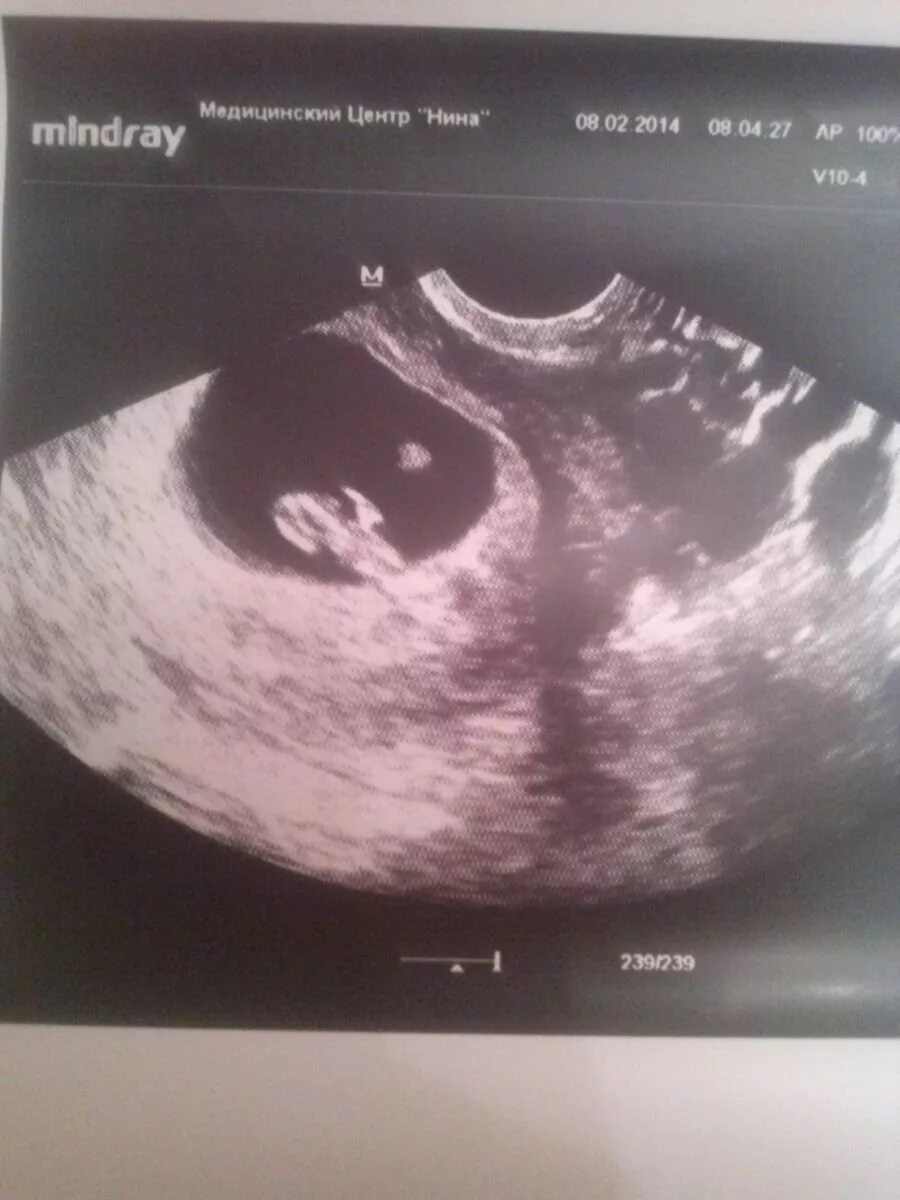

3 нед 4 дня